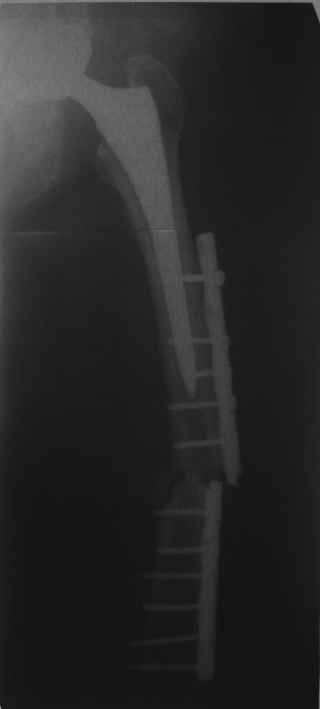

Обещанные ранее снимки Заранее спасибо.